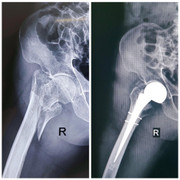

Kết quả chụp Xquang cho thấy, người bệnh bị hoại tử toàn bộ chỏm xương đùi 2 bên giai đoạn cuối. Các bác sĩ quyết định phẫu thuật thay khớp háng nhân tạo toàn phần cho người bệnh.

Ca mổ diễn ra trong 1 giờ, mặc dù kỹ thuật thay khớp háng nhân tạo toàn phần cho người bệnh không có sự khác biệt nào, song đối với người bệnh này, việc lấy ven rất khó nên các bác sĩ đã quyết định lấy ven tĩnh mạch trung ương để tiến hành dùng thuốc trong suốt quá trình mổ và sau mổ.